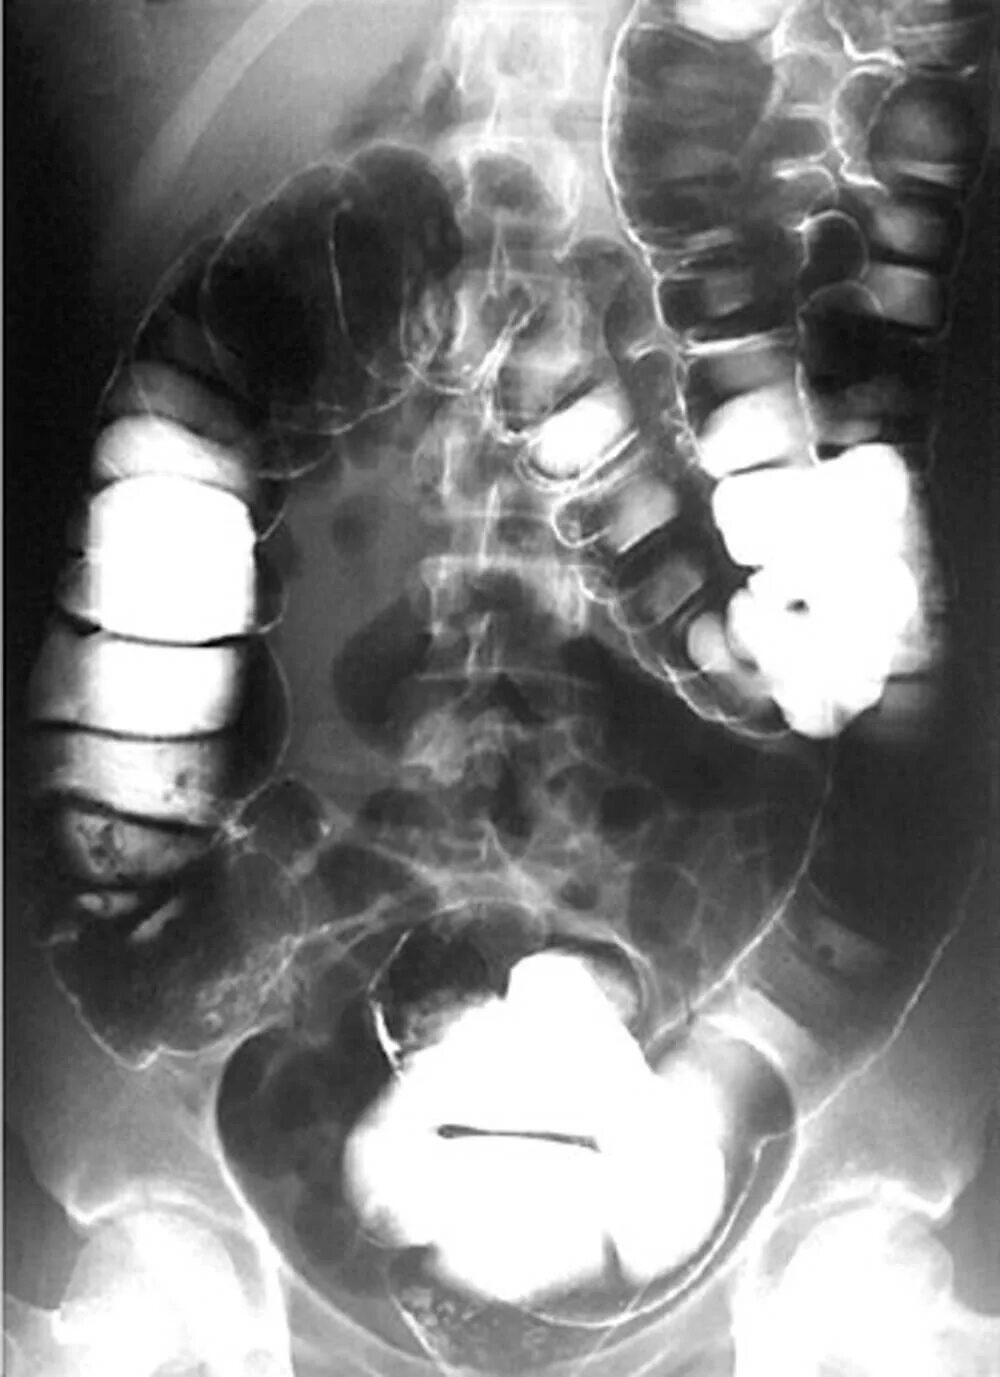

Ирригоскопия с двойным контрастированием